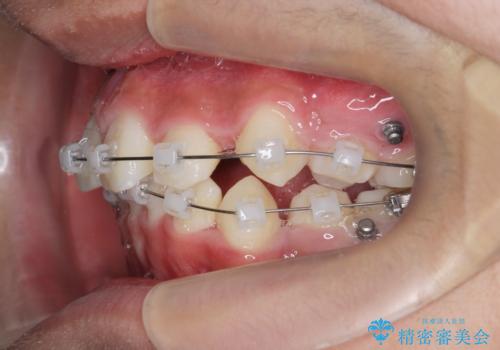

- 前歯のがたつきが原因で歯ブラシしづらい、見た目を改善したい!と矯正治療を希望され来院されました。

スペースの不足が見られるため、小臼歯の4本抜歯を行いマルチブラケットを用いた矯正治療を計画します。

噛み締めが強く、治療に時間がかかりましたが矯正治療の仕上がりに満足いただくことができました。